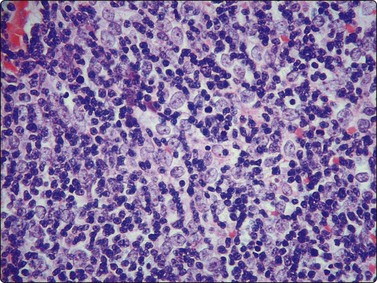

The most common sarcomas of this site include malignant fibrous histiocytoma and liposarcoma.131,132 Synovial sarcoma is well described.133 We have seen a single case of monophasic synovial sarcoma of mediastinum diagnosed on transoesophageal EUS FNB by the demonstration of SYT-SSX fusion transcripts by FISH on cell blocks, indicating X:18 translocation (all material shown here is courtesy of Dr. Anita Soma, PathWest QE II AP). (Fig. 9.10) The patient was a 45-year-old male with an 11-cm mass adjacent to the lower oesophagus, displacing the heart. Smears showed a rather bland spindle cell population but with mitotic activity. The cell block immunohistochemistry was negative for cytokeratins, CD117 and smooth muscle markers, making leiomyosarcoma and GIST unlikely. The tumor did show positive staining for CD99, BCL2 and CD34, raising the possibility of solitary fibrous tumor or synovial sarcoma. An SYT-SSX1 fusion transcript was detected by reverse transcriptase PCR, reinforcing the FISH cytogenetics. No other diagnostic procedures were undertaken (Fig 9.10).

Fig. 9.10 Synovial sarcoma

(A) Large infiltrative mass posterior to heart (Thoracic CT); (B) Loose fascicle of spindle cells including small blood vessels. Background of bare tumor nuclei (H&E, LP); (C) Loose cluster of bland spindle cells but with mitotic activity (H&E, HP); (D) Cell block, small spindle tumor cells with non-specific features (H&E, HP);(E) FISH on cell block, breakapart probe for SYT showing positive disruption of red-green-yellow components (FISH, HP); (F) FISH on cell block, fusion probe for SSX2 (green) and SYT (red) probes showing positive fusion of green and red components. (FISH, HP); (G) FISH on cell block, fusion probe for SSX2 (green) and SYT (red) probes showing positive fusion of green and red components (FISH, HP).